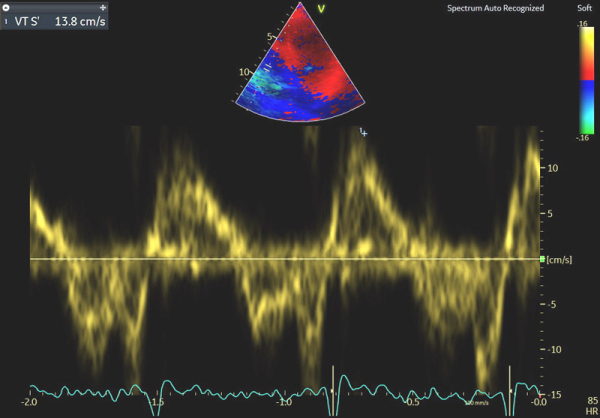

Image 5 : échocardiographie Doppler tissulaire à l’anneau tricuspide

En cas d’atteinte précoce d’amylose cardiaque, ce sont en effet les premières anomalies à pouvoir être objectivées et il peut ne pas y avoir encore d’altération marquée du SLG (cf Image 7), de signe de dysfonction diastolique VG (cf Images 3 et 4), de dilatation de l’OG (cf Image 8), de dysfonction systolique du VD (cf Image 5) et les pressions peuvent être normales.